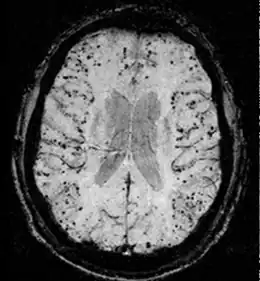

- Marqueurs en IRM cérébrale. Outre les marqueurs hémorragiques déjà mentionnés, la valeur diagnostique de quasi tous les marqueurs classiques de microangiopathie à l'IRM ont été étudiés, en particulier pour différencier l'AAC de l'angiopathie hypertensive. En particulier, plusieurs travaux se sont intéressés à la distribution des hypersignaux de la substance blanche. L'AAC semble se caractériser par une tendance à présenter des hypersignaux de substance blanche plutôt cortico-sous-corticale (proche du cortex) alors que l'angiopathie hypertensive touche plus spécifiquement les capsules externes et le tronc cérébral[18]. La présence d'hypersignaux punctiformes en IRM de diffusion a également été considéré comme un marqueur potentiel de l'AAC, mais cette association n'a pas été retrouvée dans une méta-analyse de 2018[19]. À l'heure actuelle, seule la présence de dilatation des espaces de Virchow-Robin de topographie sous-corticale a montré une bonne corrélation avec les données histologiques.